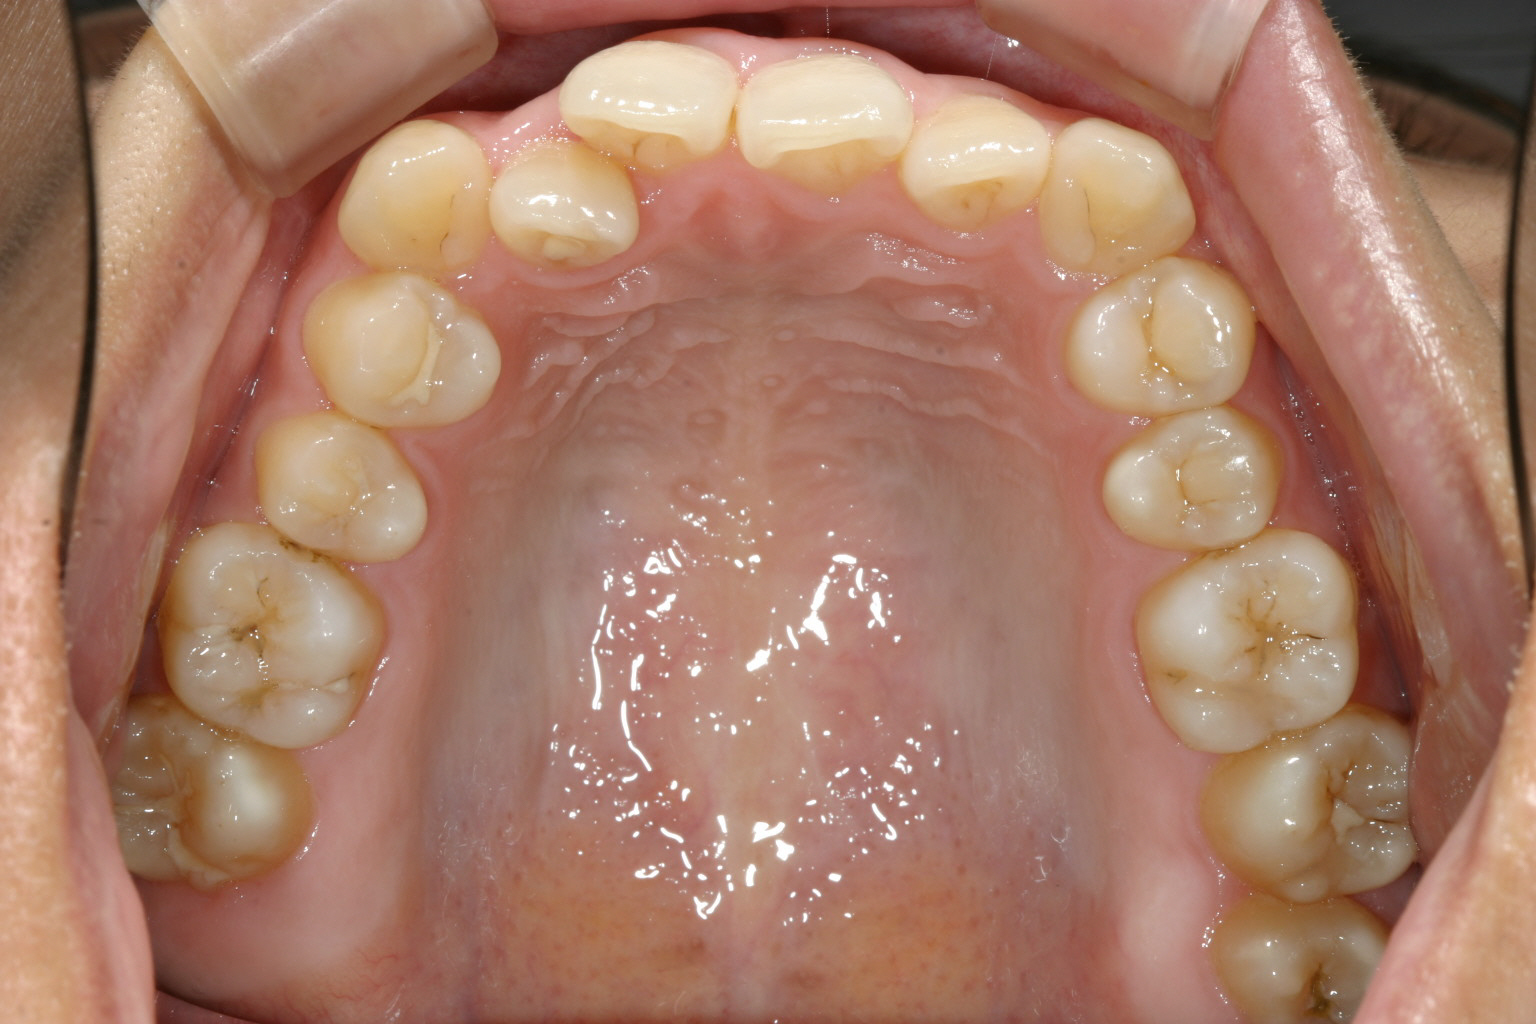

前歯に結構な叢生が見受けられます。

下顎にも上顎同様アーチがつぶれスクエアーになっています。